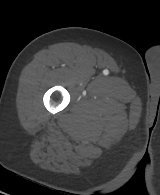

解剖学模块